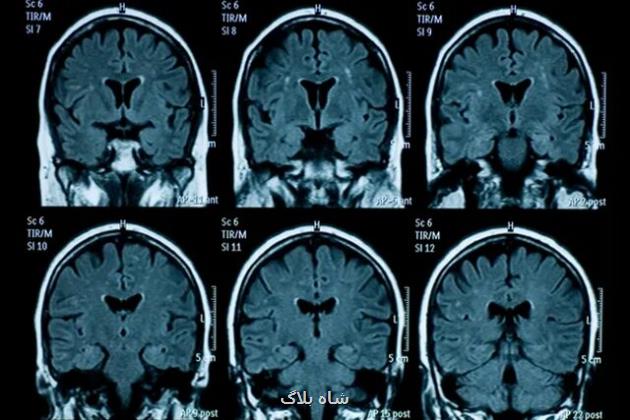

محققان اسکن های مغز ۸۱ نوجوان در ایالات متحده آمریکا را که قبل از وقوع همه گیری، بین نوامبر ۲۰۱۶ تا نوامبر ۲۰۱۹ ثبت شده بود، با اسکن مغزی ۸۲ نوجوانی که اسکن مغز آنها بین اکتبر ۲۰۲۰ تا مارس ۲۰۲۲ در طول همه گیری و بعد از لغو قرنطینه جمع آوری شده بود، مقایسه کردند.

بعد از تطبیق ۶۴ شرکت کننده در هر گروه با در نظر گرفتن عواملی همچون سن و جنسیت، محققان دریافتند که تغییرات فیزیکی که در دوران نوجوانی در مغز رخ می دهد همچون نازک شدن قشر و رشد هیپوکامپ و آمیگدال، در دوران بعد از قرنطینه در گروهی که اسکن آنها بعد از همه گیری ثبت شده بود نسبت به گروه دیگر بیشتر بوده است. این نشان داده است که چنین فرآیندهایی سرعت گرفته یا به عبارت دیگر، مغز آنها سریع تر پیر شده است.

یان گوتلیب(Ian Gotlib)، استاد روانشناسی در دانشگاه استنفورد و نویسنده اصلی این مطالعه می گوید: تفاوت سنی مغز(میان این دو گروه) حدود سه سال بود و با عنایت به این که طول قرنطینه کمتر از یک سال بود، انتظار افزایش زیادی نداشتیم.